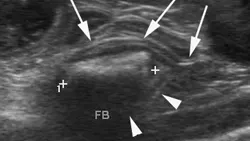

A brief abdominal ultrasound was performed and the foreign body was confirmed in a small intestinal lumen.

Outcome: This patient was cut! He was treated for dehydration and taken to surgery, where a rectangular plastic foreign body was “milked” from its location in the jejunum, backwards into the stomach, where a single gastrotomy was performed to remove the object. The severe gastroduodenal distension was secondary to complete obstruction. The patient recovered quickly and ate that same evening.